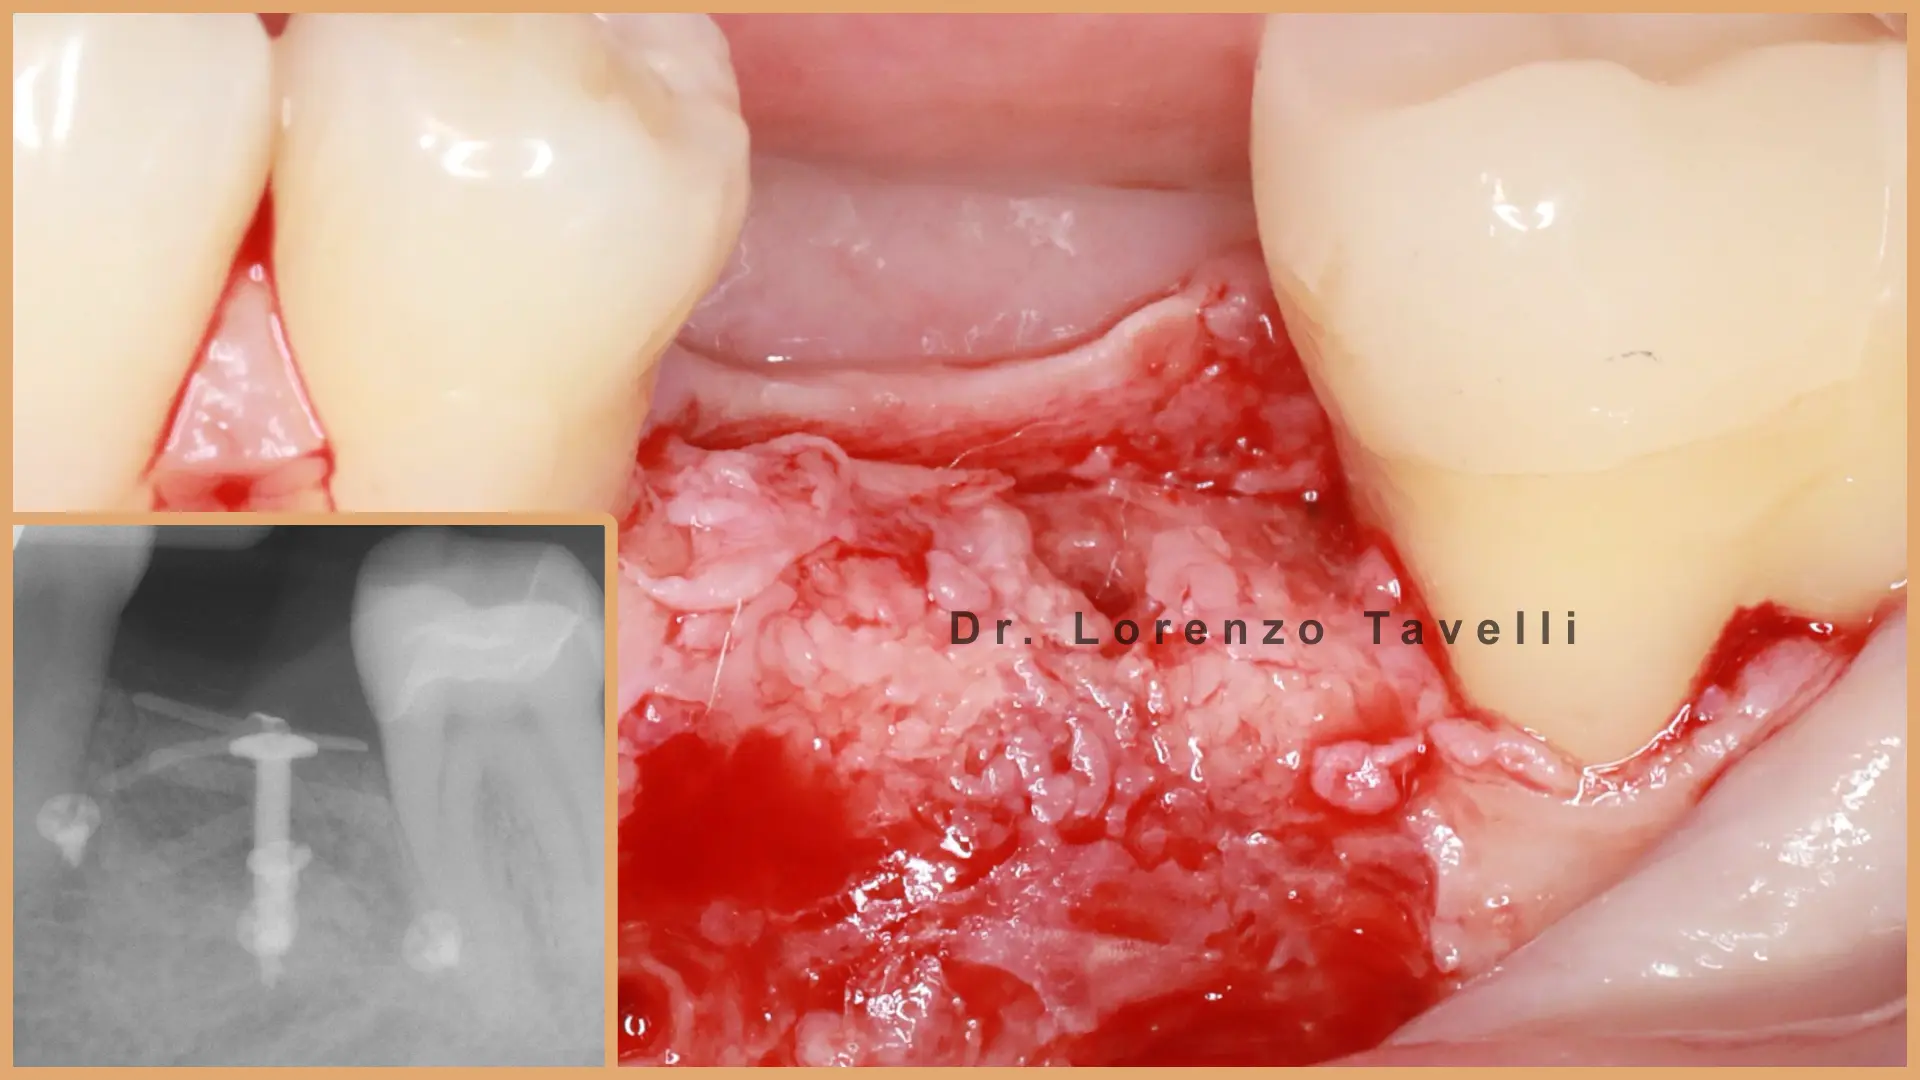

Prin prelegeri susținute de experți, videoclipuri chirurgicale și instruire practică (hands-on), participanții vor explora tehnici moderne de augmentare a țesuturilor moi, gestionarea fenotipului peri-implantar, prevenirea complicațiilor și protocoale avansate de grefare. O atenție deosebită este acordată tehnicilor minim invazive și de tip tunel, reconstrucției papilei și cazurilor complexe de implanturi în zona anterioară.

Atelierele noastre practice oferă participanților oportunitatea de a exersa tehnici contemporane de augmentare a țesuturilor moi și de grefare, sub îndrumarea experților. Prin sesiuni etapizate, aliniate cu scenarii clinice reale, participanții vor perfecționa abordările minim invazive și cele de tip tunel, reconstrucția papilei, gestionarea țesutului moale peri-implantar.

Acest curs este conceput special pentru clinicienii care doresc să își perfecționeze expertiza în implantologia estetică. Programul integrează în mod unic dovezile științifice cu aplicațiile practice, oferind o perspectivă exclusivă asupra unor cazuri clinice complexe prezentate de Dr. Lorenzo Tavelli, ce oferă o viziune aprofundată asupra parcursului său chirurgical personal și modul în care se iau cele mai bune decizii. La finalul cursului, veți dobândi un arsenal chirurgical extins și abilitățile necesare pentru a gestiona chiar și cele mai provocatoare situații în implantologie!